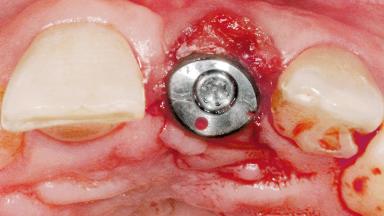

Early Placement of an Implant in a Maxillary Right Central Incisor Site

Bone Augmentation Horizontal|Simultaneous

Augmentation Materials Autogenous chips|Xenogenous|Membrane

Bone Volume Deficient horizontally, allowing simultaneous augumentation